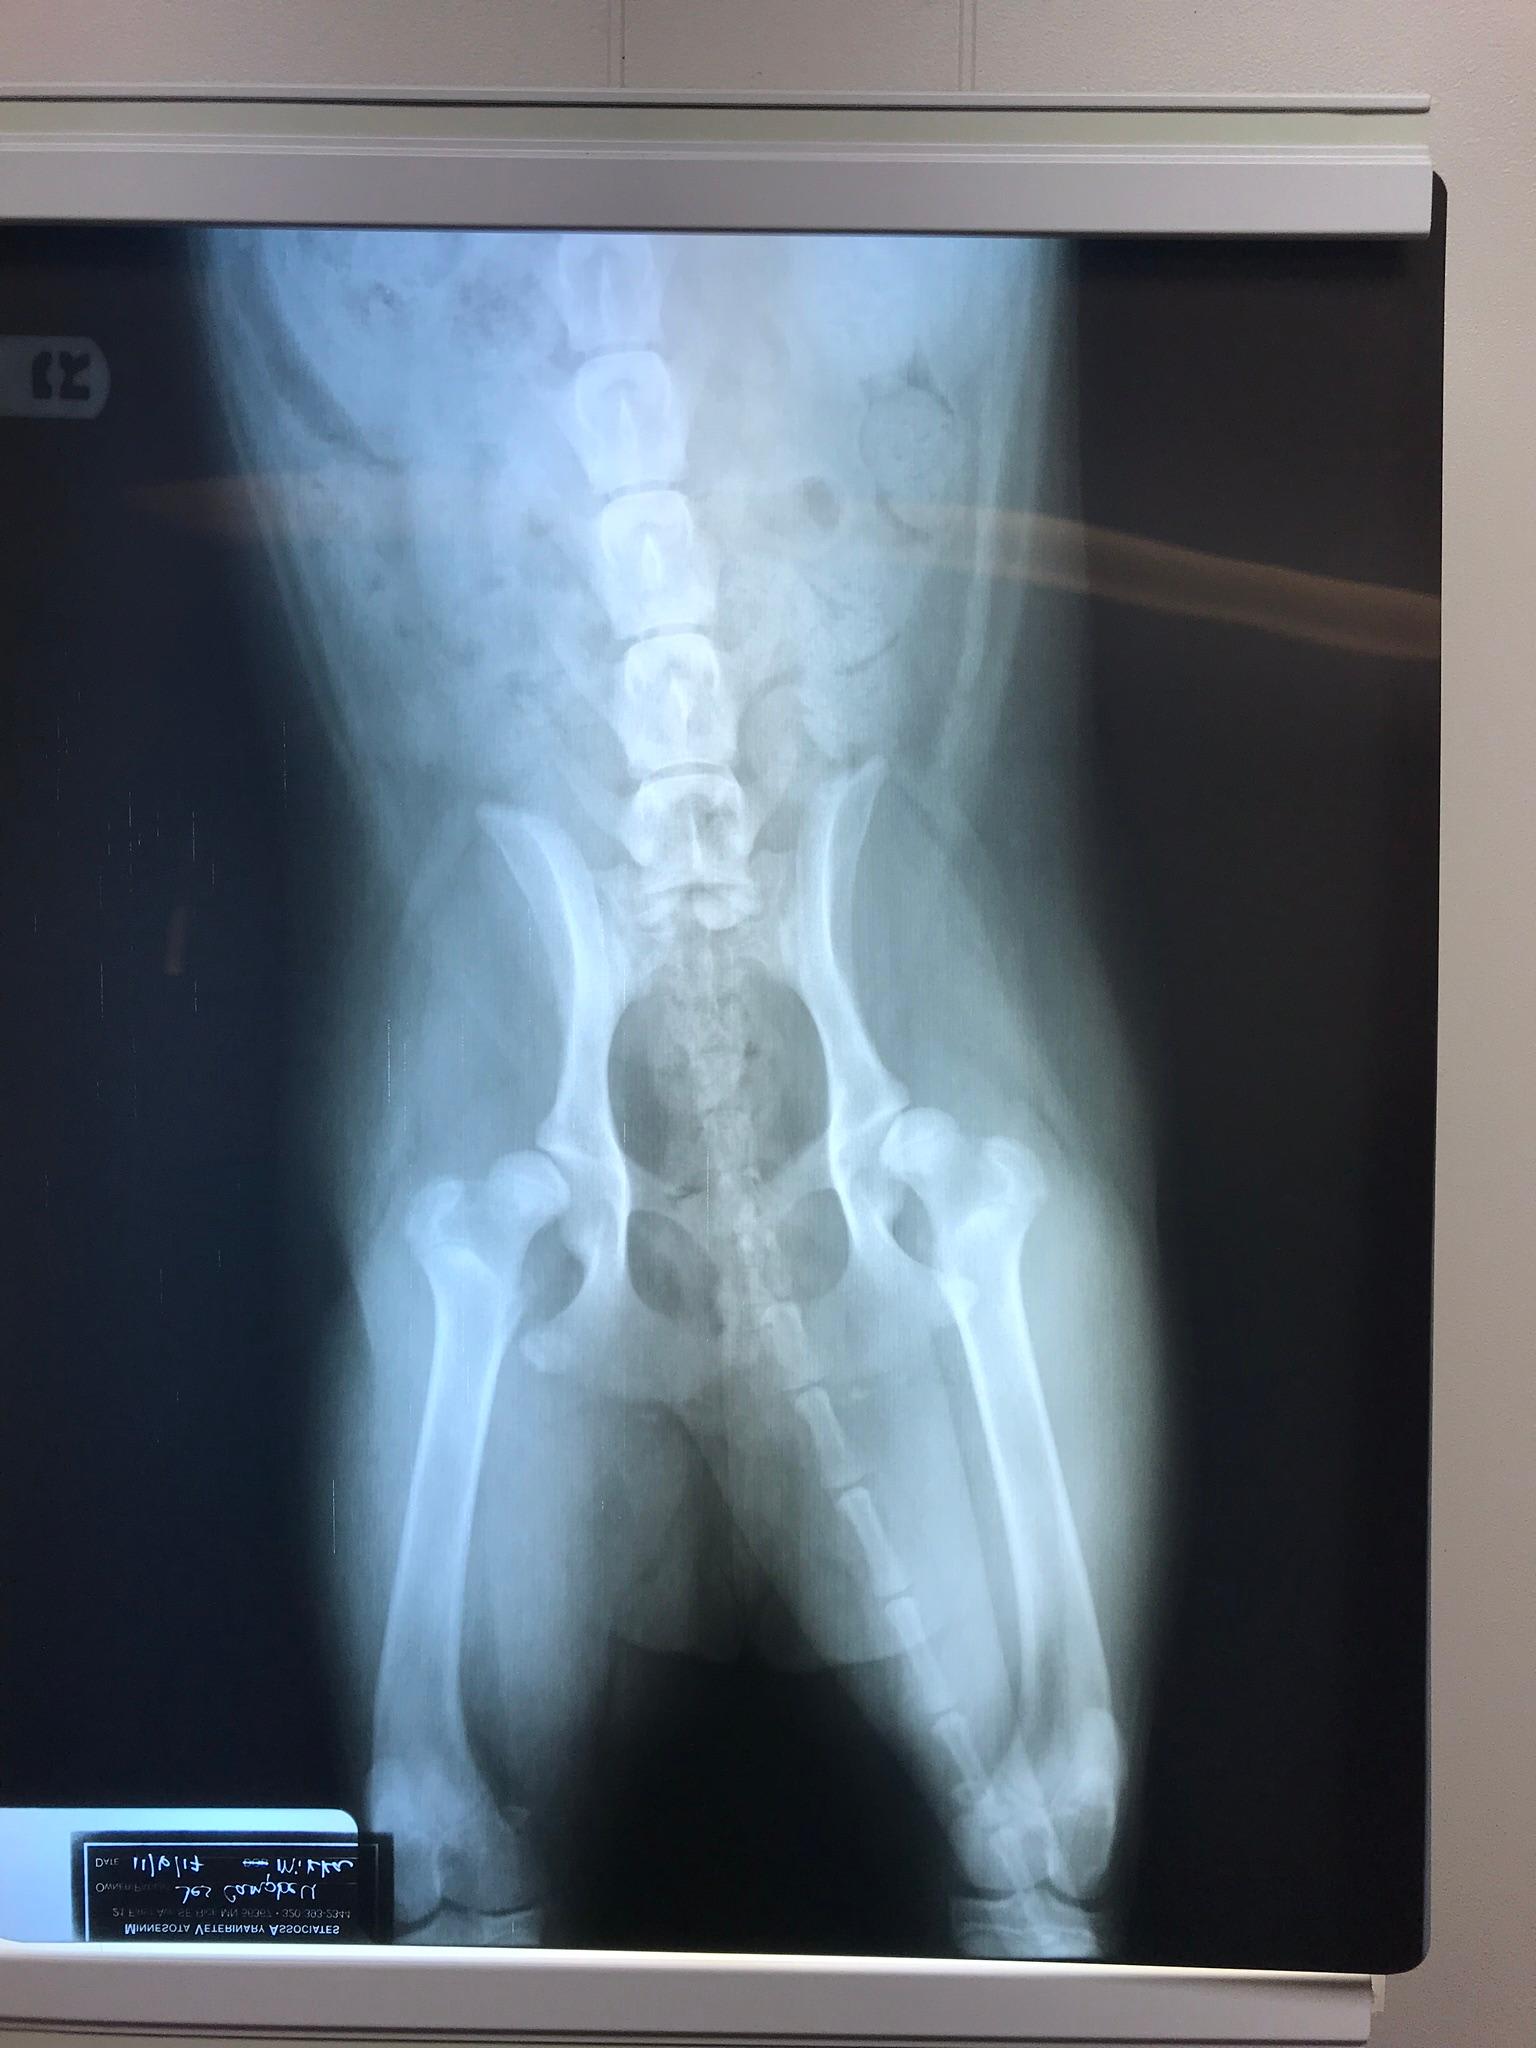

8 month old Shepard/husky/golden/staffordrshire mix with Lump on both sides of neck. More snoring sounds then usual and bad breath but she’s always had bad breath and the vet didn’t seem worried about it when we asked before but know with the lumps I’m very worried. She also has hip displasia and suppose have surgery on January 9th on one hip first.

I would have the lumps on the neck checked out for sure. I am guessing those lumps are enlarged lymph nodes. This can be serious and I doubt they would want to put her under anesthesia with enlarged lymph nodes. I would call your vet and get her back in for an exam to check her out.